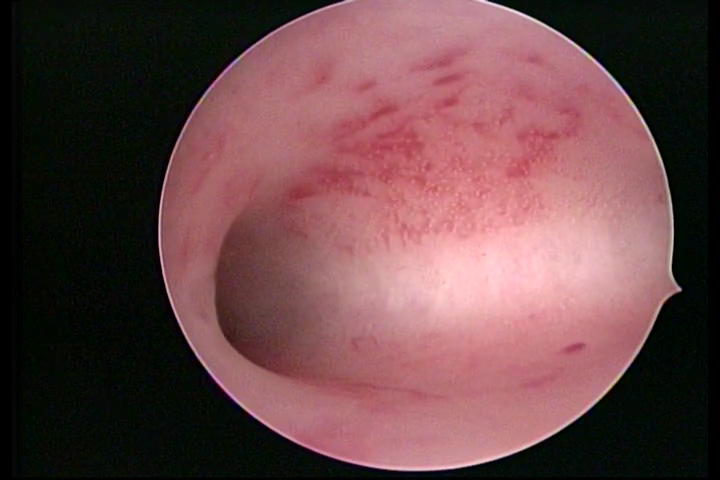

ENDOMETRITE CRÔNICA

A superfície do endométrio pode exibir alterações como um pontilhado vermelho formando novelos vasculares, o endométrio liso e hiper-vascularizado, ou com áreas vermelhas de forma intensa, com limites precisos e pontilhados branco amarelados no seu interior dando um aspecto “CASCA DE MORANGO” e uma coloração amarela pálida das comissuras fúndicas e laterais, em contraste com o vermelho intenso das paredes.